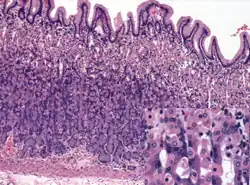

Histology of normal antral mucosa. Antral mucosa is formed by branched coiled tubular glands lined by secretory cells similar in appearance to the surface mucous cells. H&E stain.

Glands differ where the stomach meets the esophagus and near the pylorus.[26] Near the gastroesophageal junction lie cardiac glands, which primarily secrete mucus.[25] They are fewer in number than the other gastric glands and are more shallowly positioned in the mucosa. There are two kinds - either simple tubular glands with short ducts or compound racemose resembling the duodenal Brunner's glands. Near the pylorus lie pyloric glands located in the antrum of the pylorus. They secrete mucus, as well as gastrin produced by their G cells.[27]